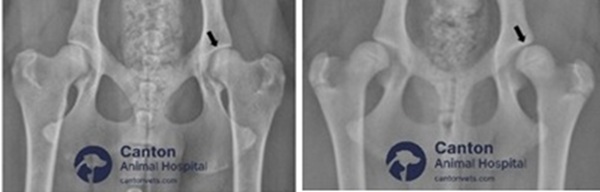

Pubic Symphysiodesis in Puppies with Hip Dysplasia

What Is Juvenile Pubic Symphysiodesis (JPS)?

Juvenile Pubic Symphysiodesis (JPS) is a preventive surgical procedure performed in young puppies to reduce the risk or severity of hip dysplasia. The procedure modifies the growth of the pelvis, improving the alignment of the hip joints before full skeletal maturity.

JPS is a minimally invasive surgery that involves cauterizing the growth plate in the pubic bone, which alters the way the pelvis develops, leading to better coverage of the femoral head within the hip socket. This improved joint conformation reduces the likelihood of future arthritis and hip pain.

Diagnostic Confirmation:

Must be identified early using PennHIP radiographs, which measure joint laxity and risk of hip dysplasia.

How Is JPS Surgery Performed?

Minimally invasive procedure done under general anesthesia.

A small incision is made to access the pubic symphysis (the cartilage between the left and right pelvic bones).

Heat or electrocautery is applied to stop further growth of the pubic symphysis, causing the pelvis to rotate slightly outward as the puppy grows.

The result is better coverage of the hip joint, reducing joint laxity and future arthritis risk.